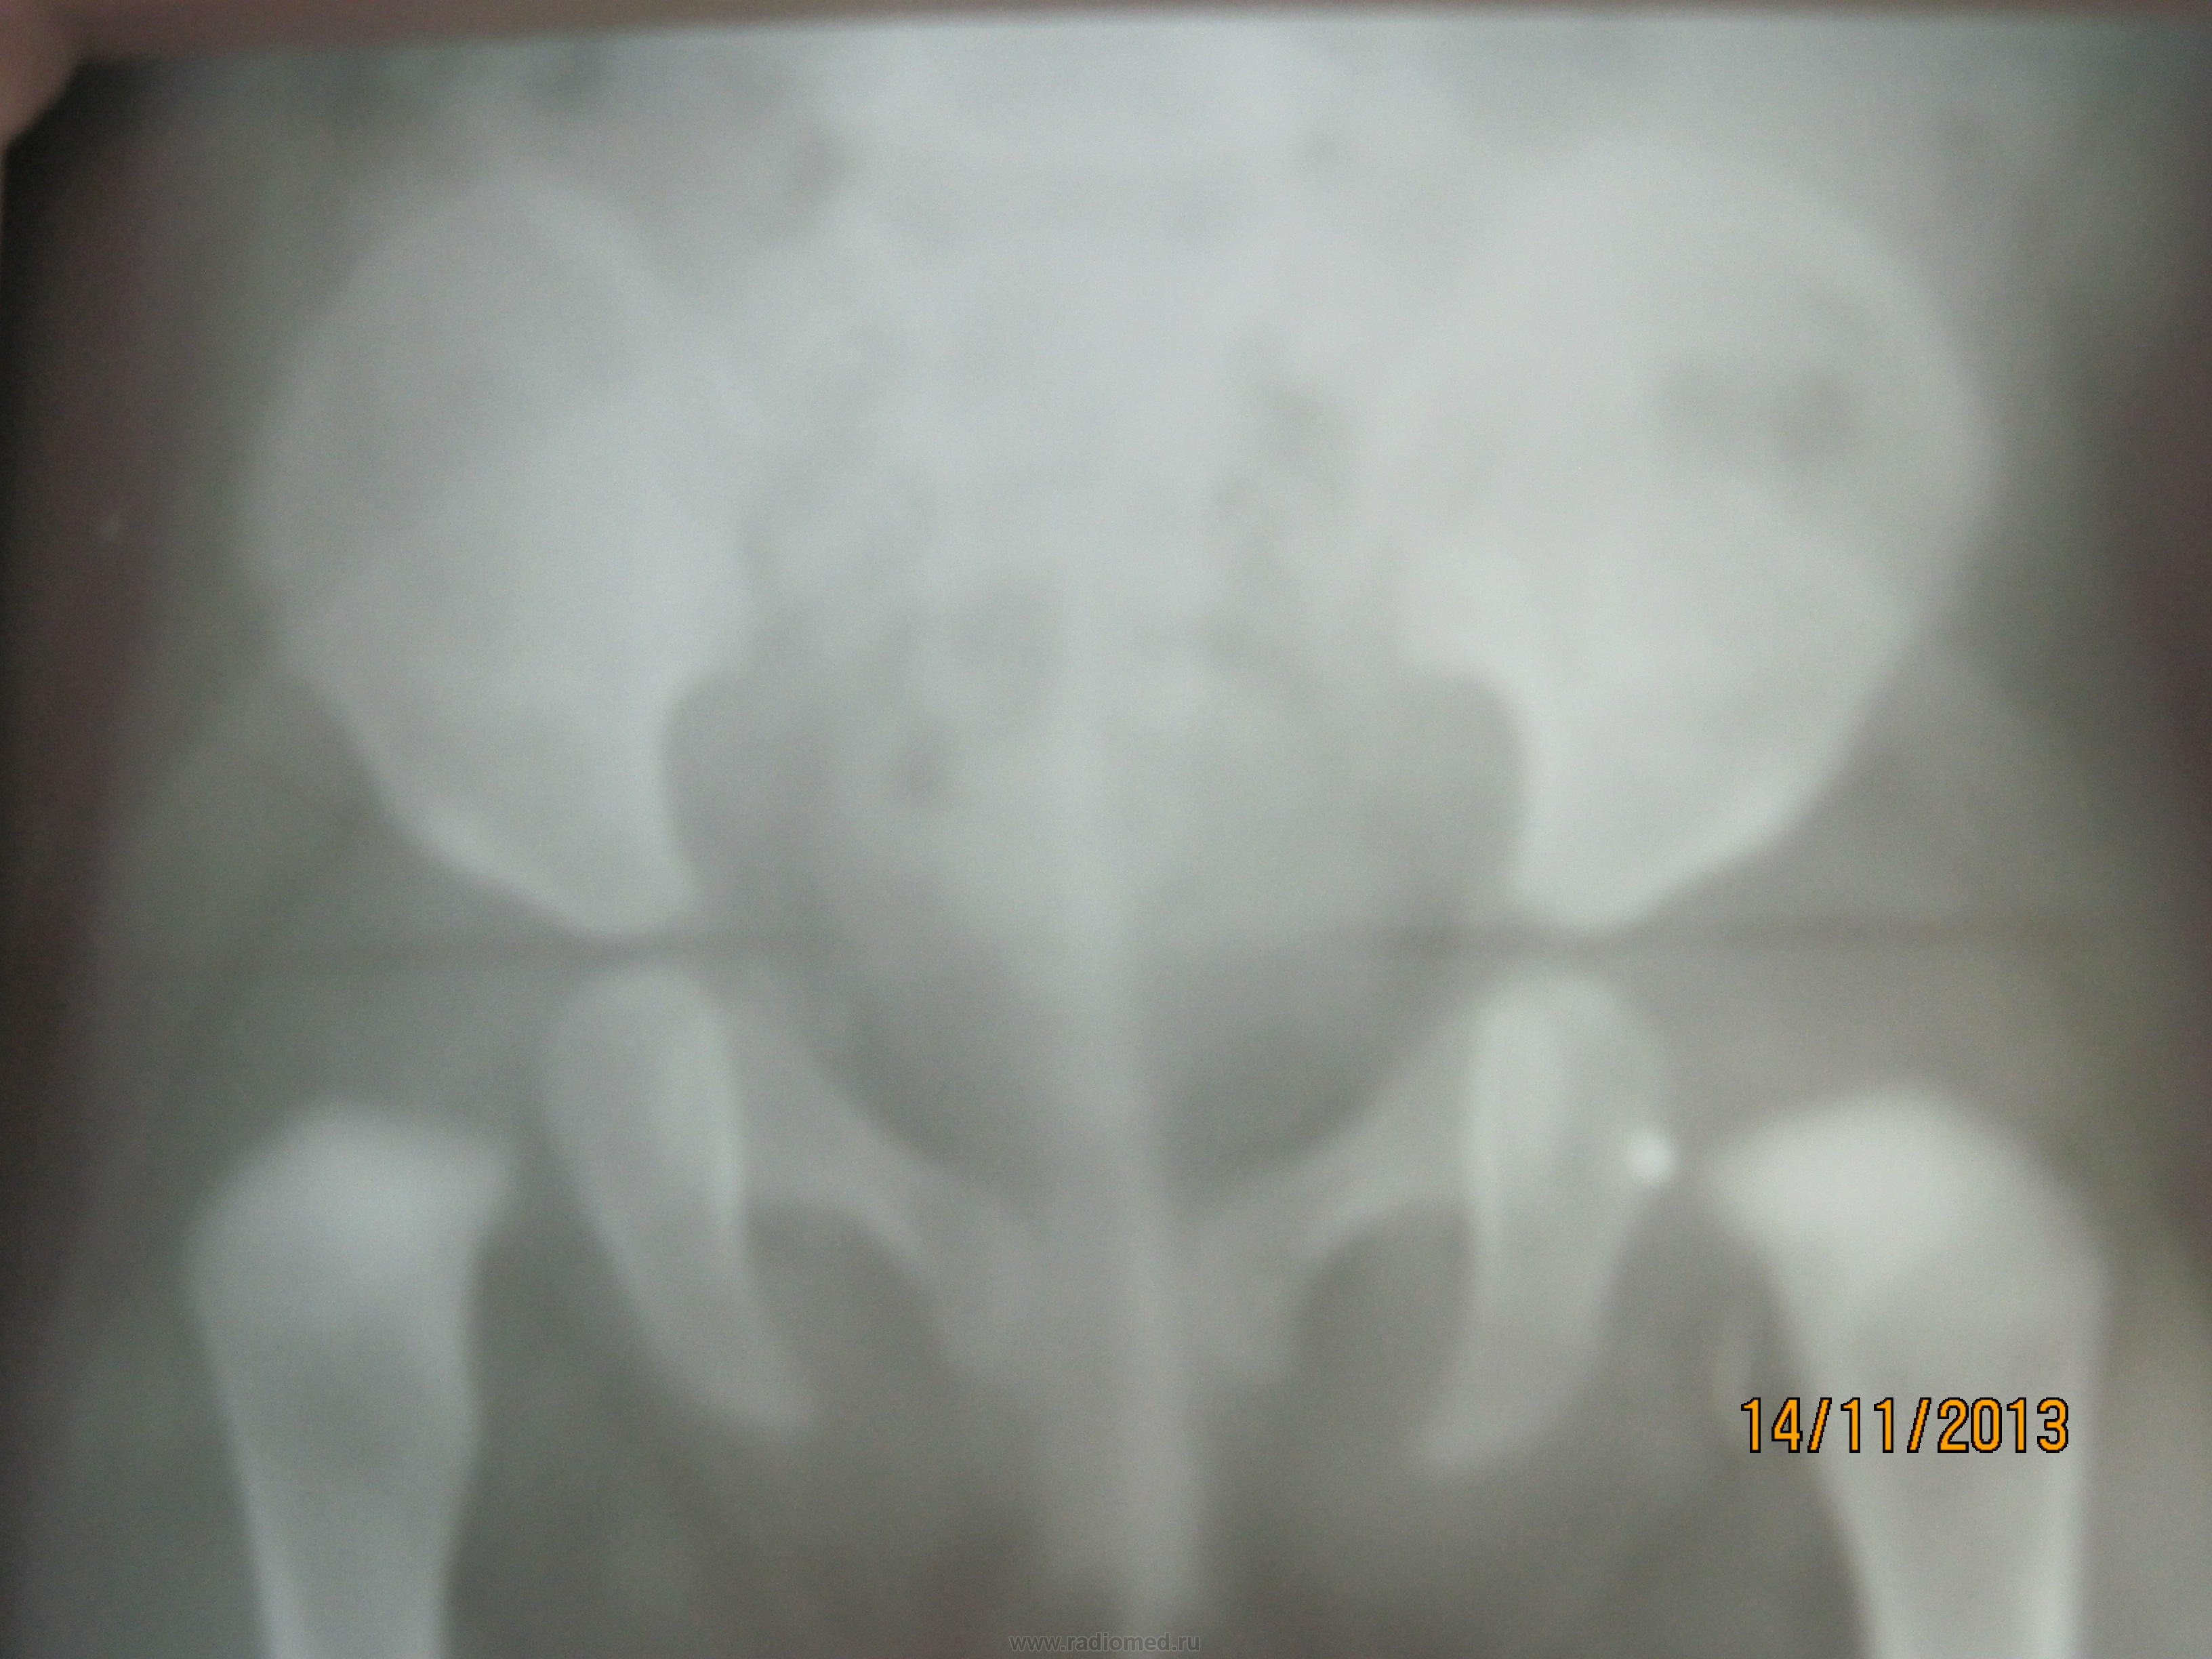

Девочка 5месяцев, ацетабулярный угол справа 29, слева 32, остальное не изменено( укладывается в норму)

Требуется точный возраст (дата рождения), стандартная разметка снимка с углами и линиями. В пограничных случаях (то ли да, то ли нет) даю описание с углами и размерами, и оставляю на ортопеда. Справа впечатление легкой сегментации линии Шентона, но, может, из-за укладки?

Да вполне приемлемый для диагностики снимок. Главное - симметричный. Из - за облучения проблемной зоны повторять смысла не вижу. Легкая дисплазия слева. А если ядер окостенения еще нет то их и не видно...

Есть ли дисплазия ТБС? или всё-таки нет?